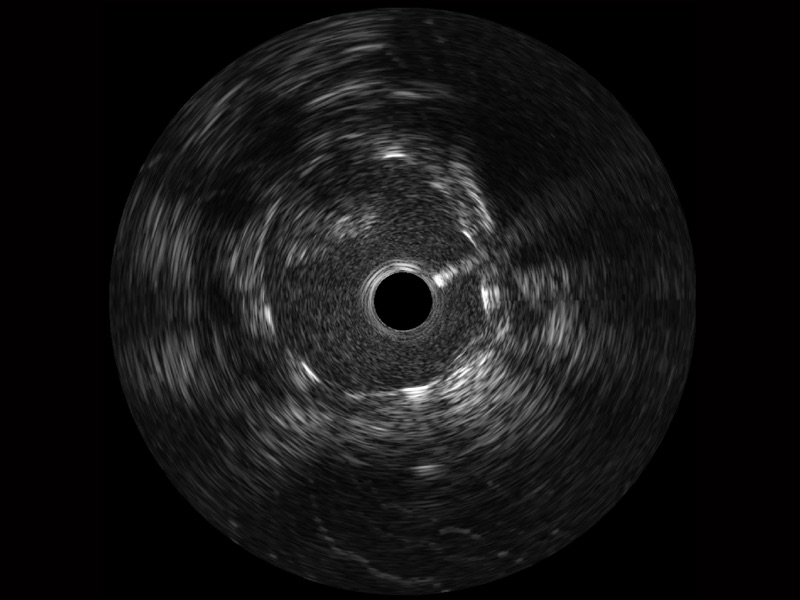

1xBET宽频IVUS图像

传统IVUS图像

对比传统IVUS导管成像,1xBET宽频IVUS图像的近场支架梁显影更细腻,远场中膜外血管仍清晰可辨,兼顾远中近,兼顾分辨力与穿透深度